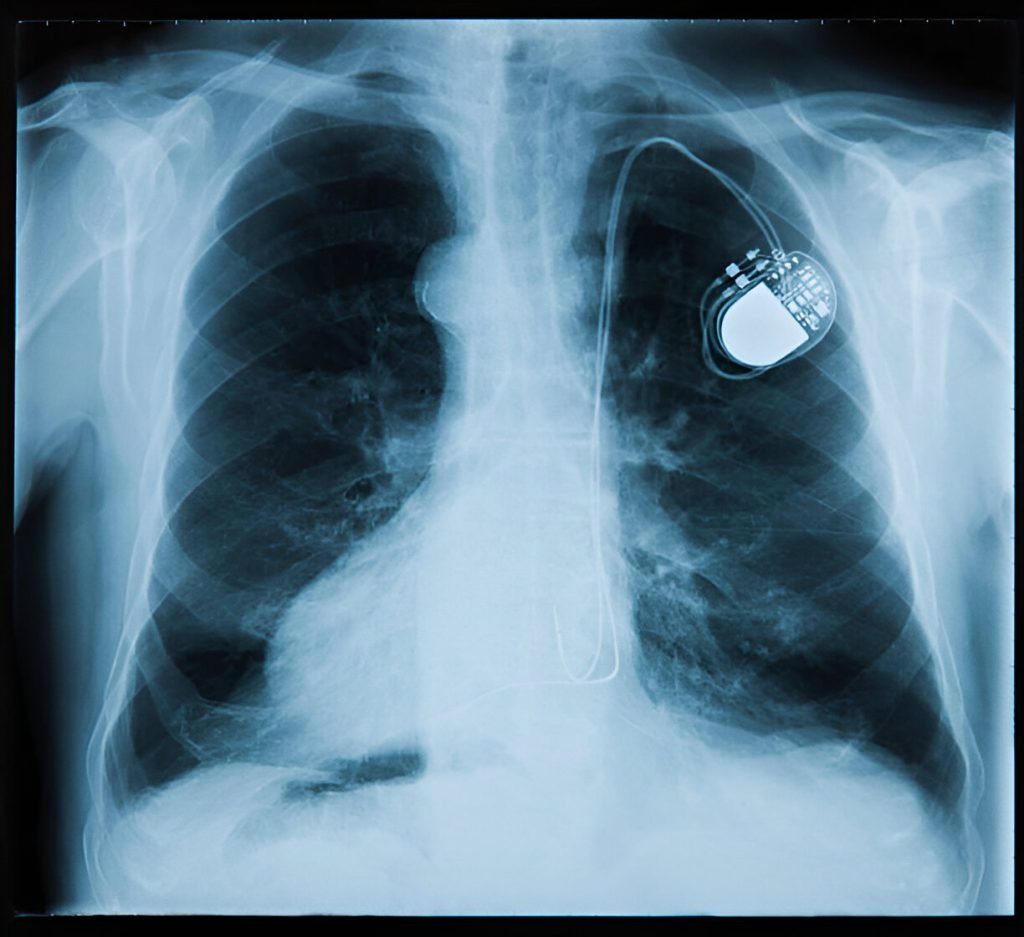

A pacemaker is a small device implanted in the chest to help regulate the heart’s rhythm. It monitors the heart’s electrical activity and, when necessary, sends electrical impulses to stimulate a heartbeat.

A pacemaker consists of a pulse generator (battery and electronic circuitry) and leads (wires) that connect the device to the heart. The pacemaker rhythm is adjusted to meet the specific needs of the patient, ensuring the heart beats at a normal rate.